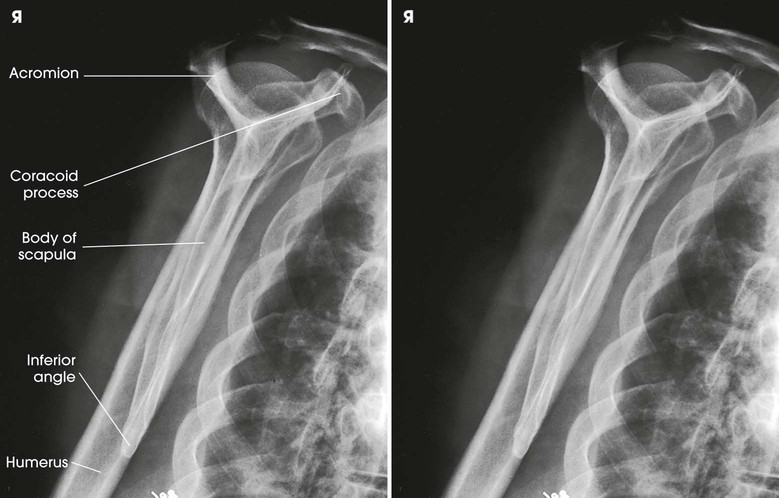

The scapular Y is shown on an oblique image of the shoulder. In the normal shoulder, the humeral head is directly superimposed over the junction of the Y (Fig. 5-37). In anterior (subcoracoid) dislocations, the humeral head is beneath the coracoid process (Fig. 5-38); in posterior (subacromial) dislocations, it is projected beneath the acromion. An AP shoulder projection is shown for comparison (Fig. 5-39).